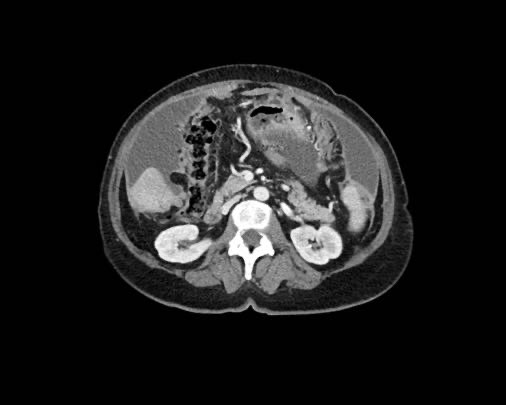

Rãnh cạnh đại tràng

Bất kỳ vị trí nào trong ổ bụng được phủ bởi phúc mạc đều có thể là đích đến của các nốt cấy ghép phúc mạc.

Các vị trí điển hình khác bao gồm rãnh cạnh đại tràng, túi cùng trực tràng-bàng quang hoặc trực tràng-tử cung, dây chằng liềm và mặt bụng của cơ hoành.